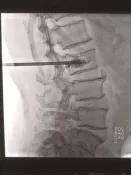

手術(shù)中情況

4月21日,我院骨科孫守全專家小組為老人進(jìn)行了PKP手術(shù),術(shù)后當(dāng)天老人腰背部疼痛銳減,己能坐起吃飯。術(shù)后第二天就能下床大小便,生活已能基本自理。七天后,老人順利出院!按照常規(guī)治療方法,需臥床三個月,還有可能出現(xiàn)尿路感染、肺部感染等等一系列并發(fā)癥。這結(jié)果與現(xiàn)在相比真有天壤之別!據(jù)了解,PKP手術(shù)為脊椎的微創(chuàng)手術(shù),手術(shù)時間短、創(chuàng)傷小,出血少,止痛效果明確,恢復(fù)比較快。尤其是對于高齡衰弱的患者而言,采用PKP手術(shù)治療,患者承擔(dān)的手術(shù)風(fēng)險極大地減少,并且避免了長期臥床所導(dǎo)致的潛在并發(fā)癥。但該手術(shù)部位鄰近脊柱總神經(jīng),需要施術(shù)者嫻熟的手術(shù)技巧和細(xì)心大膽的手術(shù)操作。我院骨科在濰坊市較早引入椎體成形術(shù),目前已經(jīng)為近千名老人解除了"腰痛"病痛。